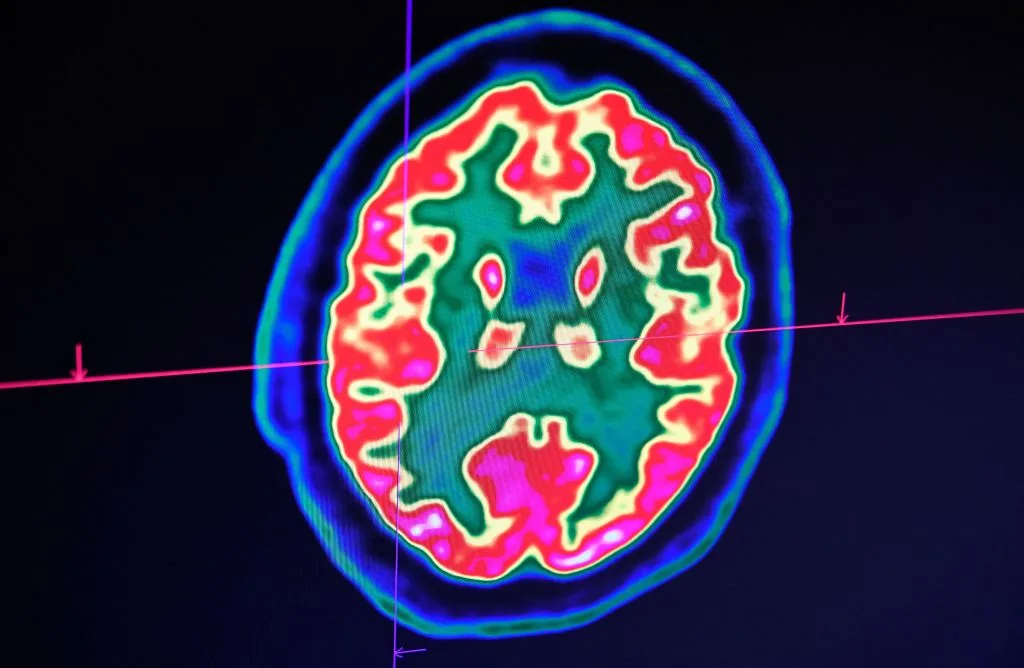

Đặc biệt khi đánh giá sớm được cho là một chiến lược cứu sống, vì giờ đầu tiên rất quan trọng để xác định chấn thương sọ não; nếu không được điều trị kịp thời, các chấn thương sọ não như chấn động não có thể để lại những hậu quả bất lợi lâu dài. Nhưng sau một vụ tai nạn, các triệu chứng tổn thương não không thể xuất hiện ngay lập tức và các phương pháp chẩn đoán hình ảnh tiên tiến như chụp CT và MRI – vốn chỉ có ở bệnh viện, thường cần thiết để chẩn đoán.